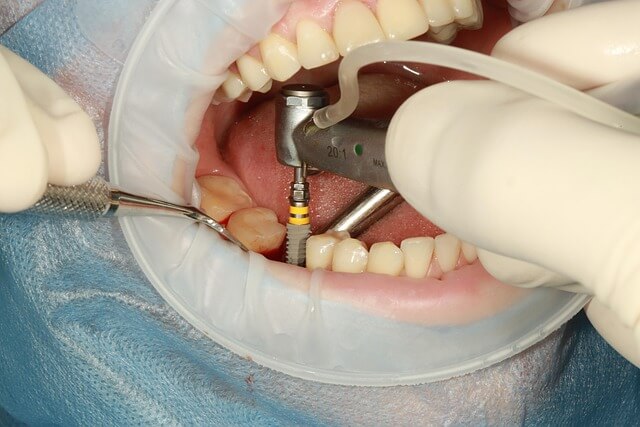

풍치 치료는 초기에 제대로 관리하면 회복이 빨라요. 저는 우선 잇몸 상태를 점검하고, 치석 제거를 병행하며 상태를 개선했습니다. 단 풍치가 심한 경우엔 전문적인 관리가 반드시 필요합니다. 자세한 관리법 보러가기.

풍치 초기 증상이 나타났다면 절대 기다리지 말고 바로 관리에 들어가야 합니다. 풍치는 시간이 지나면 잇몸 뼈가 손상되어 회복이 어려워집니다. 붓기나 통증이 심하지 않더라도 일단 구강 위생 관리를 강화하고, 1~2주 내 개선이 없으면 전문가에게 점검을 받는 것이 중요합니다.

가정에서도 충분히 실천할 수 있는 기본 관리법은 다음과 같습니다.

- 소금물로 하루 두 번 가글하기

- 치약은 잇몸 보호 성분이 들어간 제품으로 선택하기

- 양치 후 혀 세정으로 세균 번식 억제

- 탄수화물 음식 섭취 후 반드시 양치

저는 이렇게 3주간 실천한 결과, 피가 나던 잇몸이 단단해지고 아침 입 냄새도 줄었습니다. 풍치는 적절한 시기에 제대로 관리만 해도 충분히 회복이 가능하다는 걸 몸소 느꼈어요.